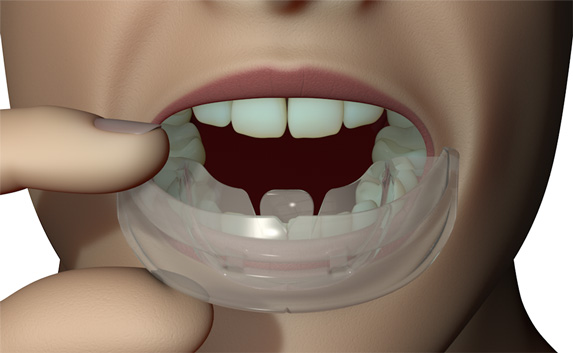

The TMJ Appliance®, which does not require any special fitting, is designed to act as an initial diagnostic and treatment tool for TMJ disorder. It works by decompressing the temporomandibular joint (TMJ), helps to correct mouth breathing and tongue posture habits, as well as limits bruxing. The TMJ Appliance® achieves TMJ disorder symptom relief immediately by alleviating pressure on the TMJ and relaxes the muscles around the jaw and neck.

The TMJ Appliance® treats both intracapsular and extracapsular disorders—TMJ clicking and pain (intracapsular) as well as pain referred from the craniomandibular muscles (extracapsular).